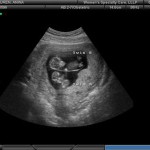

Photo échographie:

Une échographie à 11 semaines montrera les contours clairement visibles du petit homme. Sur un équipement haut de gamme avec une localisation particulièrement bonne du bébé, vous pouvez déjà déterminer son sexe. Cependant, les données peuvent être inexactes.

Avec une grossesse gémellaire (ou triple), le développement de chaque enfant est à peu près le même qu'avec une grossesse unique. Dans le même temps, les petits hommes peuvent différer sensiblement (de plusieurs millimètres) de croissance. C'est tout à fait normal.